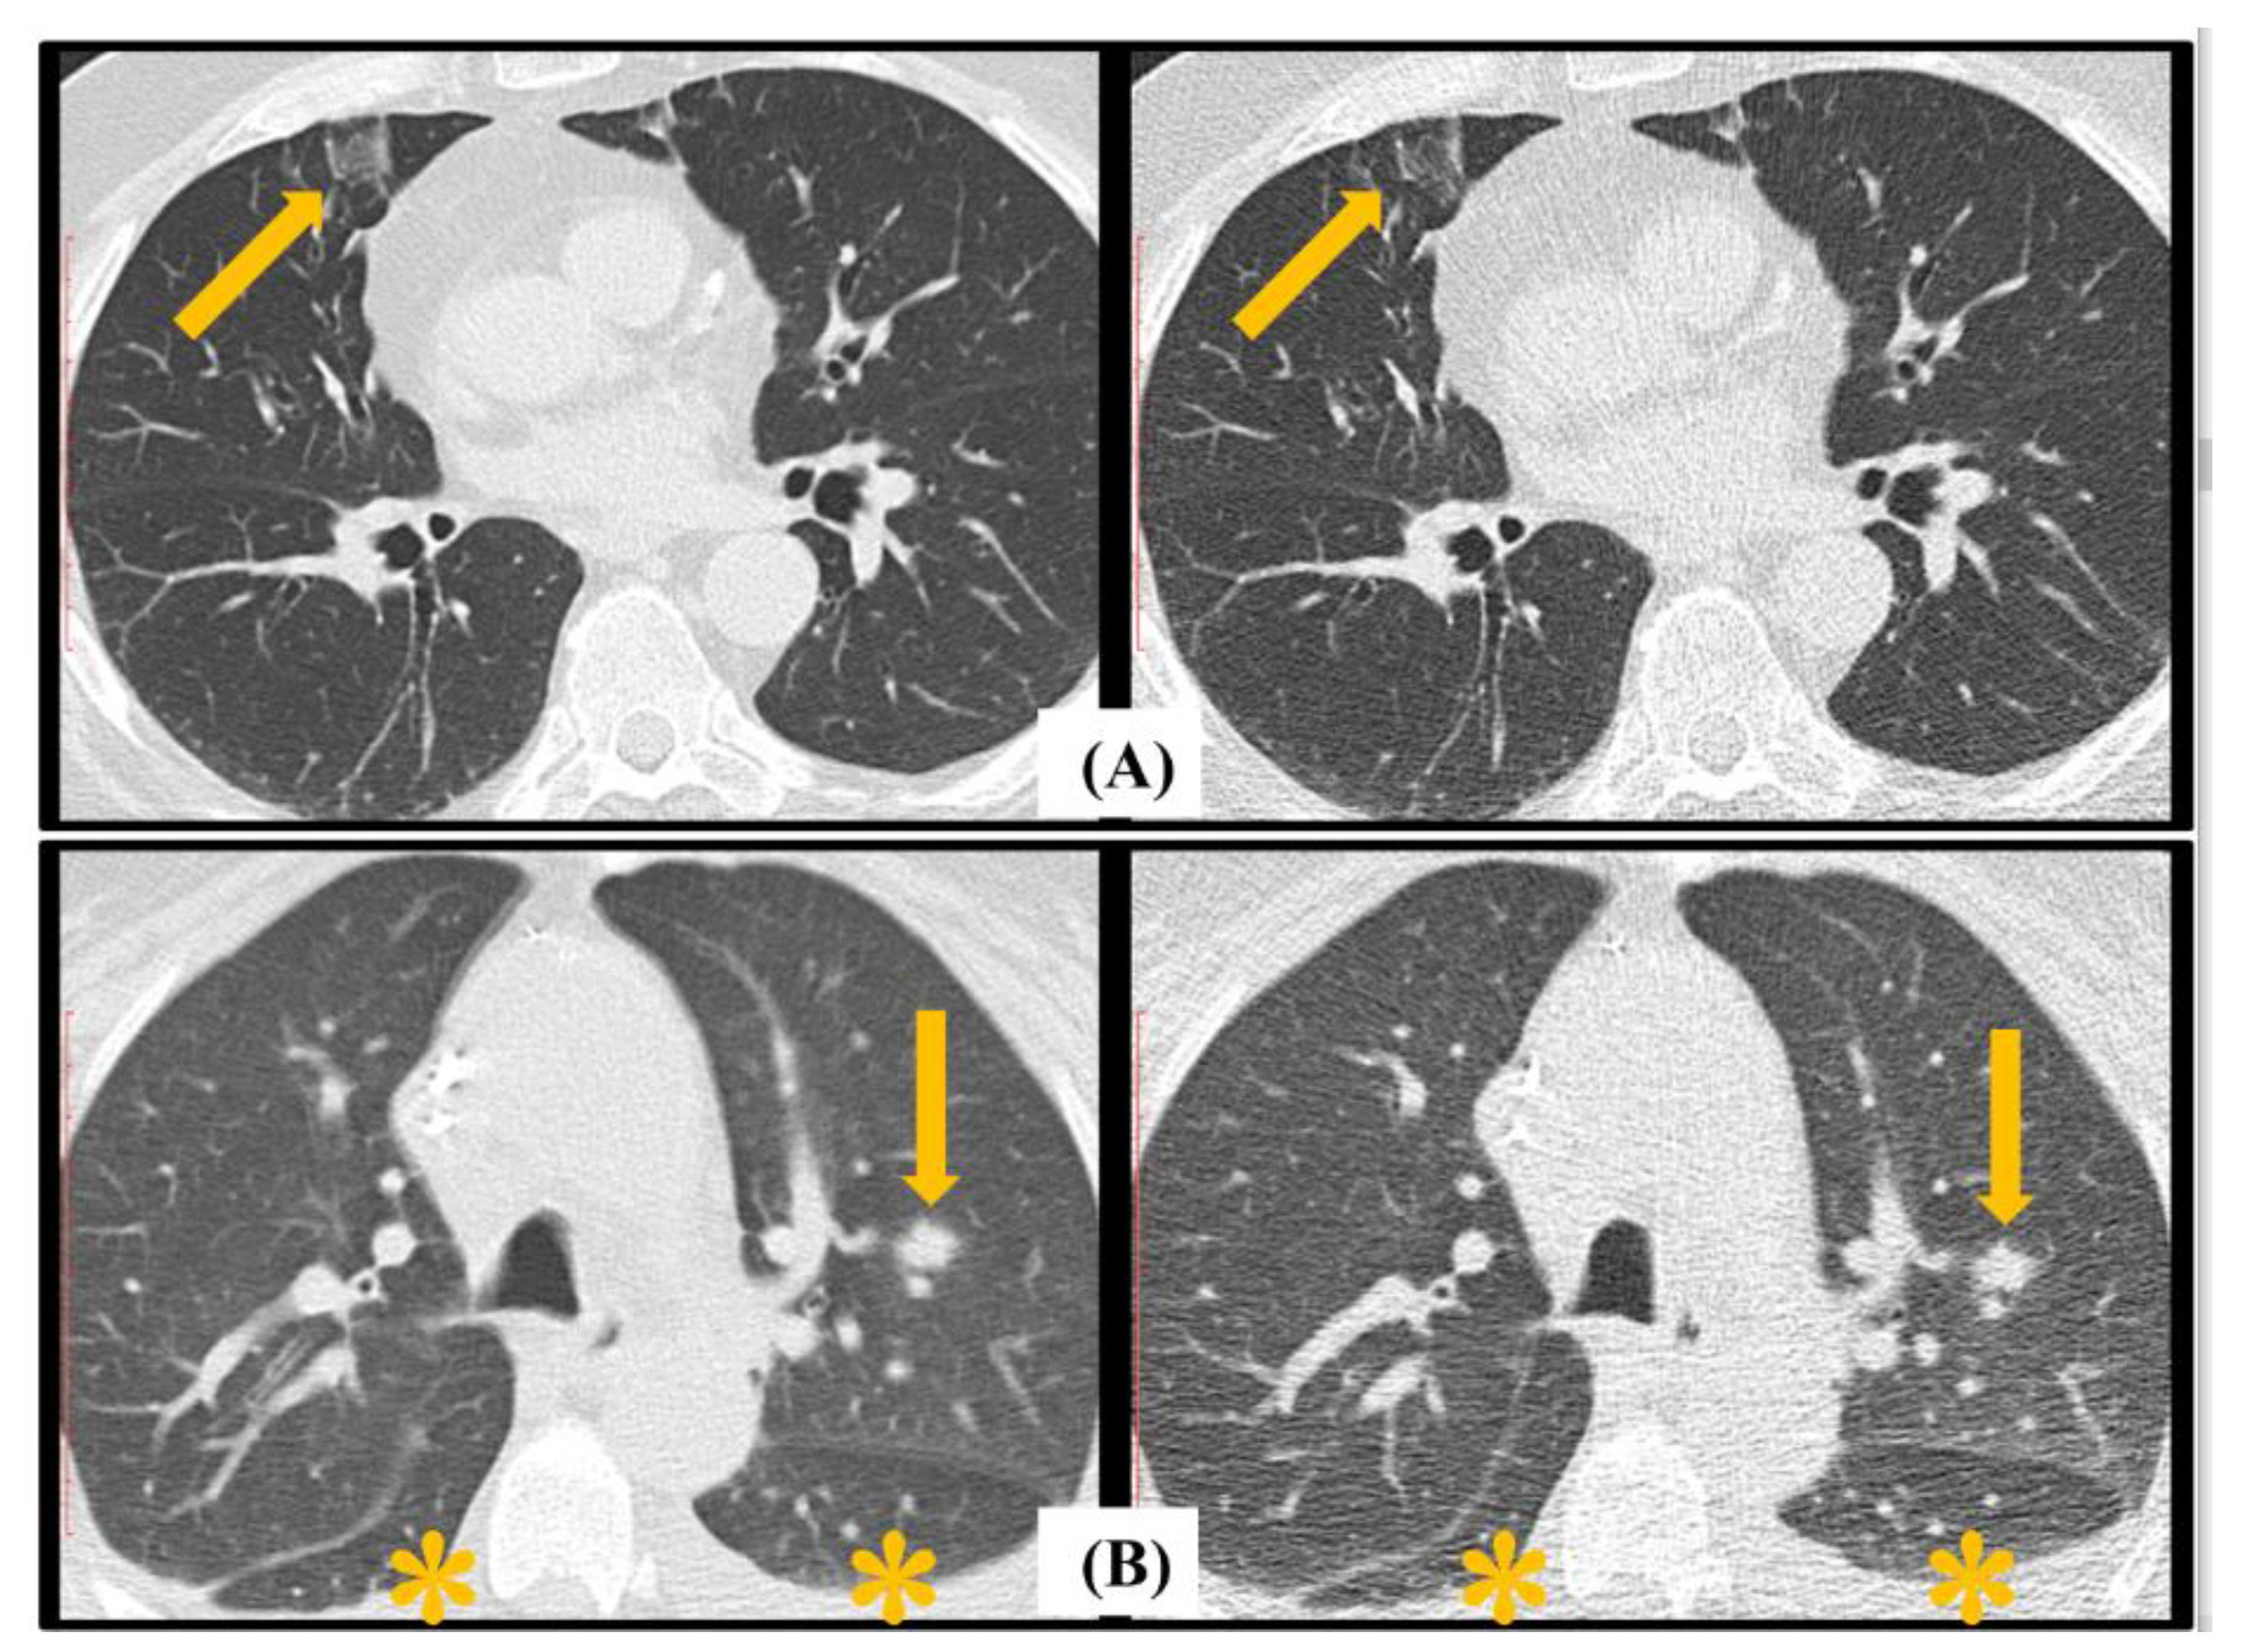

4.3. EORTC Radiological Findings Assessment

| Any Major Radiological Sign * | 24 | 2 | 2 | 72 | 92.3% | 97.3% | 96.0% |

| Macro Nodule | 4 | 0 | 0 | 96 | 100% | 100% | 100% |

| Halo Sign | 2 | 1 | 0 | 97 | 66.7 | 100.0 | 99.0 |

| Cavitation | 2 | 0 | 0 | 98 | 100.0 | 100.0 | 100.0 |

| Consolidation | 22 | 2 | 3 | 73 | 91.7 | 96.1 | 95.0 |

| Any Minor Radiological Sign * | 71 | 13 | 3 | 13 | 84.5% | 81.3% | 84.0% |

| Nodules (4–10 mm) | 49 | 13 | 8 | 30 | 79.0 | 78.9 | 79.0 |

| GGO | 56 | 16 | 3 | 25 | 77.8 | 89.3 | 81.0 |

| Any major findings | 0.83 [0.45–0.99] | 0.82 [0.46–0.97] |

| Macro nodule | 0.87 [0.2–0.97] | 0.83 [0.27–0.94] |

| Halo sign | 0.74 [0.07–0.93] | 0.95 [0.29–0.98] |

| Cavitation | 0.92 [0.25–0.98] | 0.96 [0.27–1] |

| Consolidation | 0.84 [0.45–0.97] | 0.85 [0.49–0.98] |

| EORTC Minor Findings | ||

| Any minor findings | 0.65 [0.22–0.93] | 0.66 [0.32–0.92] |

| GGO | 0.67 [0.33–0.92] | 0.69 [0.39–0.94] |

| Nodules (4–10 mm) | 0.58 [0.22–0.98] | 0.51 [0.25–0.89] |